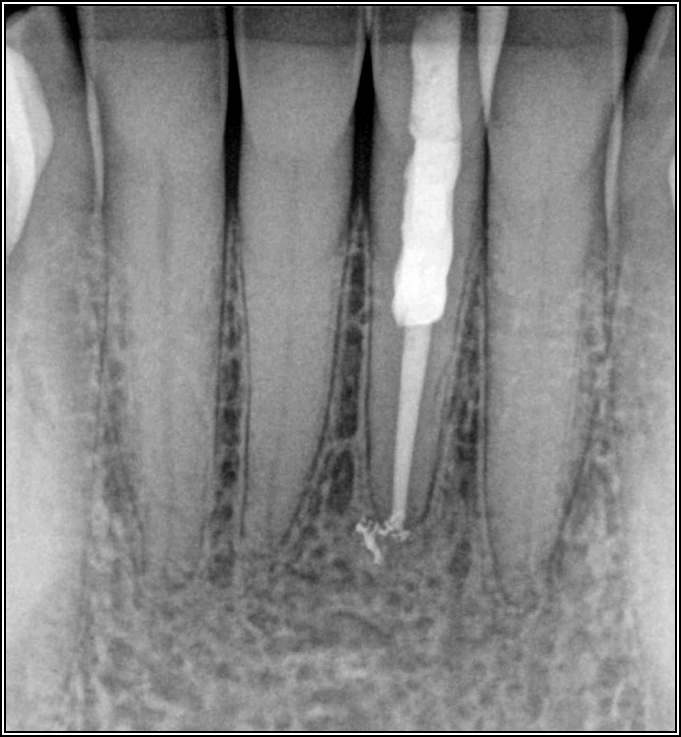

The options, therefore, were to extract it and put a bridge or an implant in later when funds were acquired, or, as was done in this case, perform an intentional replant. The clinician extracted the tooth, cut it, placed MTA, and then put it back under occlusion using sutures—although the clinician would normally put composite in each corner to maintain it and would not etch. Usually after 2 weeks, there is stability. Figure 15 shows the postoperative radiograph, and Figure 16 shows a radiograph 4.5 years later. The patient's probing went from 3 to 4 mm, but overall it was a success because something is always lost coronally, whether the case is a replant or an implant.

Fig 15. Postoperative radiograph.

Figure 15